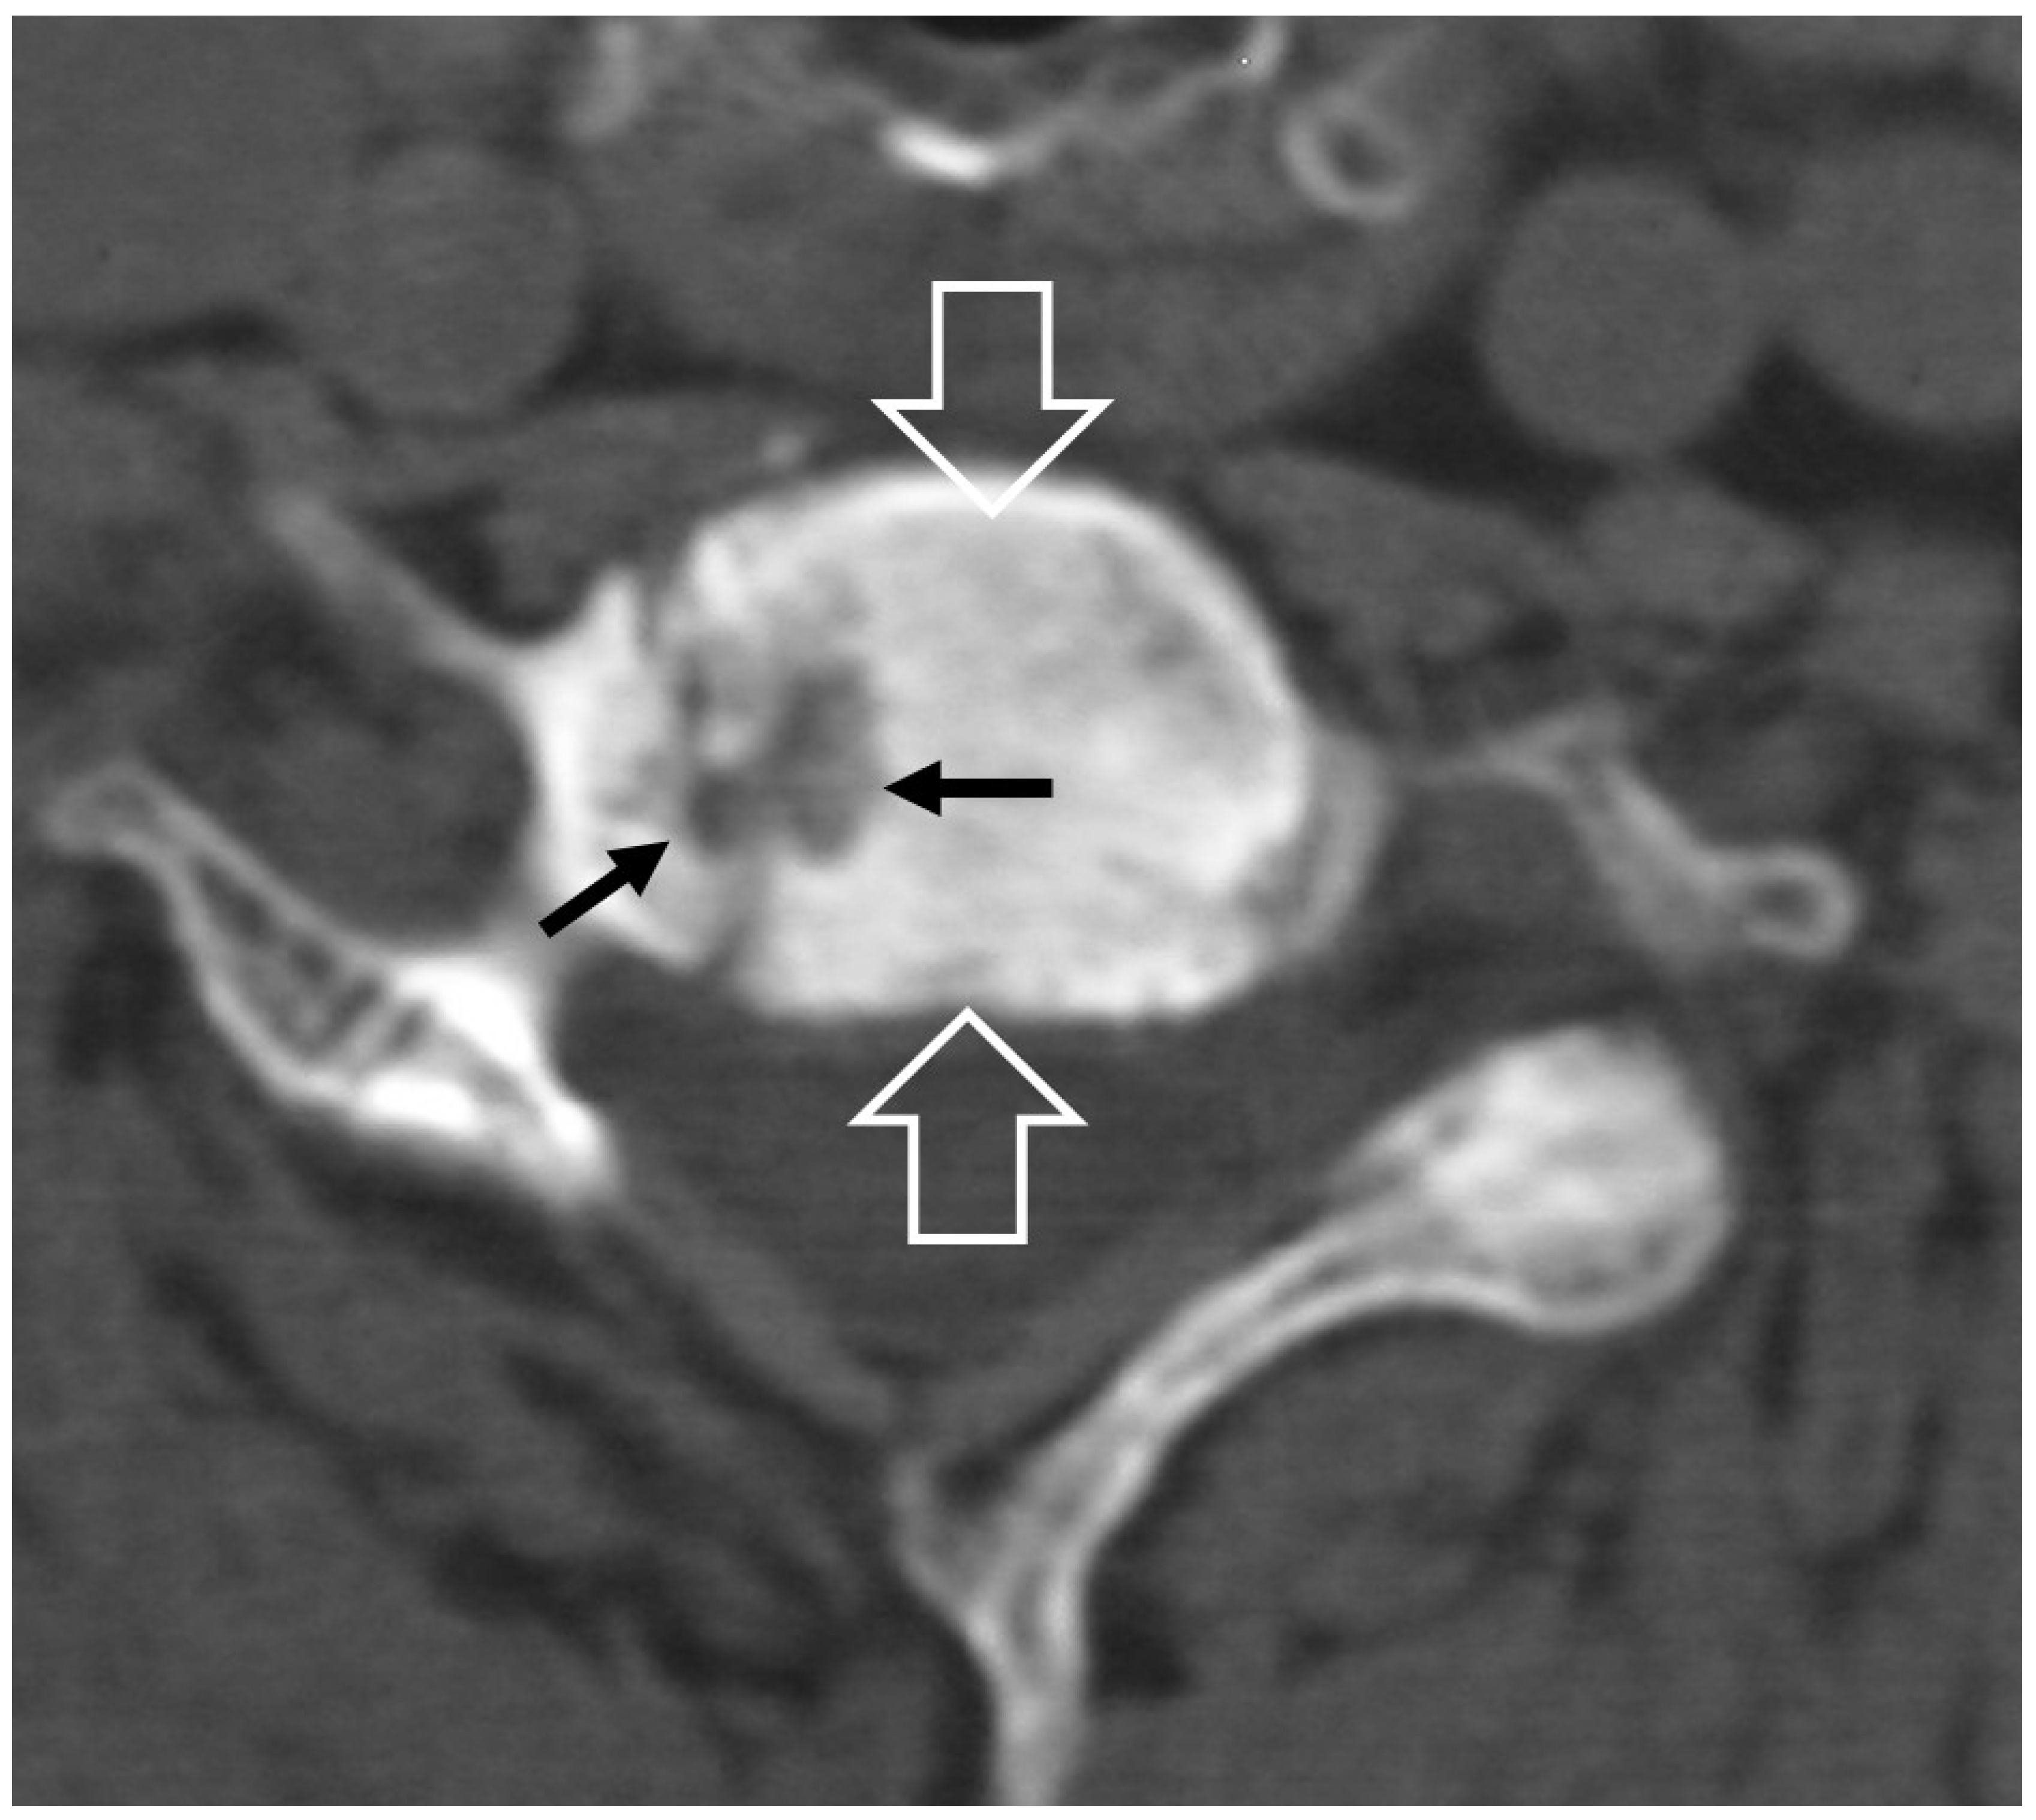

2.1.5. Crystal Deposition

2.1.6. Post-Operative Aseptic Discitis